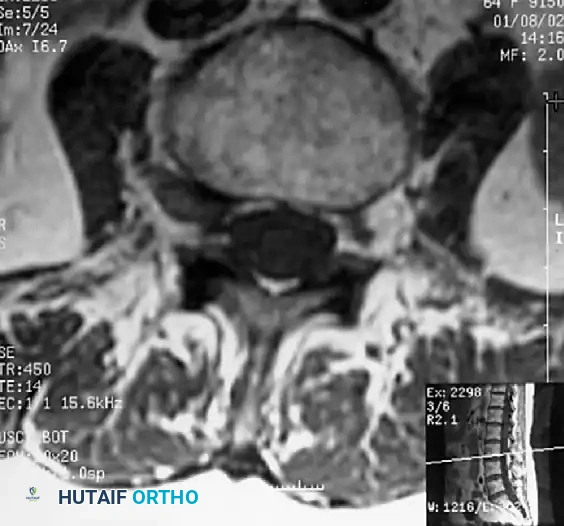

Magnetic Resonance Imaging (MRI):

MRI is the gold standard, providing excellent soft-tissue contrast to evaluate the intervertebral discs, ligamentum flavum, and neural elements. T2-weighted axial and sagittal images are critical for assessing the degree of cerebrospinal fluid (CSF) effacement and nerve root compression.